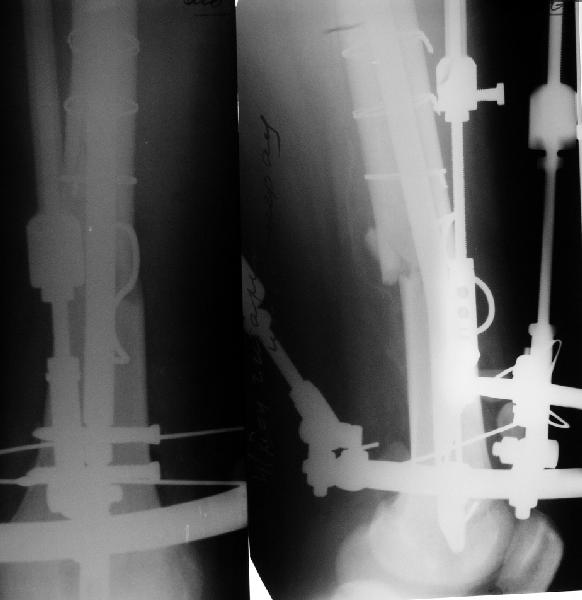

30.09.04 на операции выявлен вывих бедра и перелом голени на этой же стороне. Остесинтез бедра все же выполнен, и по заживлении раны пациент переведен к нам. Кроме того у пациента нейропатия седалищного нерва на этой же стороне. В нашей клинике планируется наложение аппарата таз-бедро, для постепенного низведения бедра с последующим открытым вправлением, замена фиксатора на запираемый гвоздь и блокируемый остесинтез голени. Вариант с первичным эндопротезированием мы не рассматривали из-за юного возраста пациента. Вопрос с чего начать? Кроме того, сгибание в коленном суставе в настоящее время (95 градусов) затрудняет остеосинтез голени.Стоит-ли менять гвоздь? Или же спилить торчащий конец во время открытого вправления? Может, попробовать все сделать одномоментно? Заранее спасибо.

Просьба простить за длительное молчание, не было фотоаппарата, чтобы перенести рентгенограммы. Больного прооперировали в прошлый четверг, как и предполагали, голень проблем не доставила(настолько, что даже не ввели дистальные винты по ряду причин: срок после травмы, целая малоберцовая, последующая длительная ходьба без нагрузки, да и гвоздь сел плотно). Изначально планировали после удаления фиксатора антеградно завести стержень и утопить конец, но вопрос был исчерпан, когда выяснилось, что все имеющиеся стержни слишком длинные, пришлось ретроградно забить большеберцовый гвоздь, после рассверливания; серьезные проблемы возникли с устранением ротации. В вертельной области сломали стержень-джойстик(привет установщику эндопротеза), дальнейшие манипуляции проводили пучком спиц и стержнем с кондуктором. Закончили все аппаратом таз-бедро. Решили что возможные огрехи с ротацией устраним после открытого вправления. Снимки прилагаю. Спасибо за участие в обсуждении. Обязуюсь информировать о дальнейших этапах лечения.